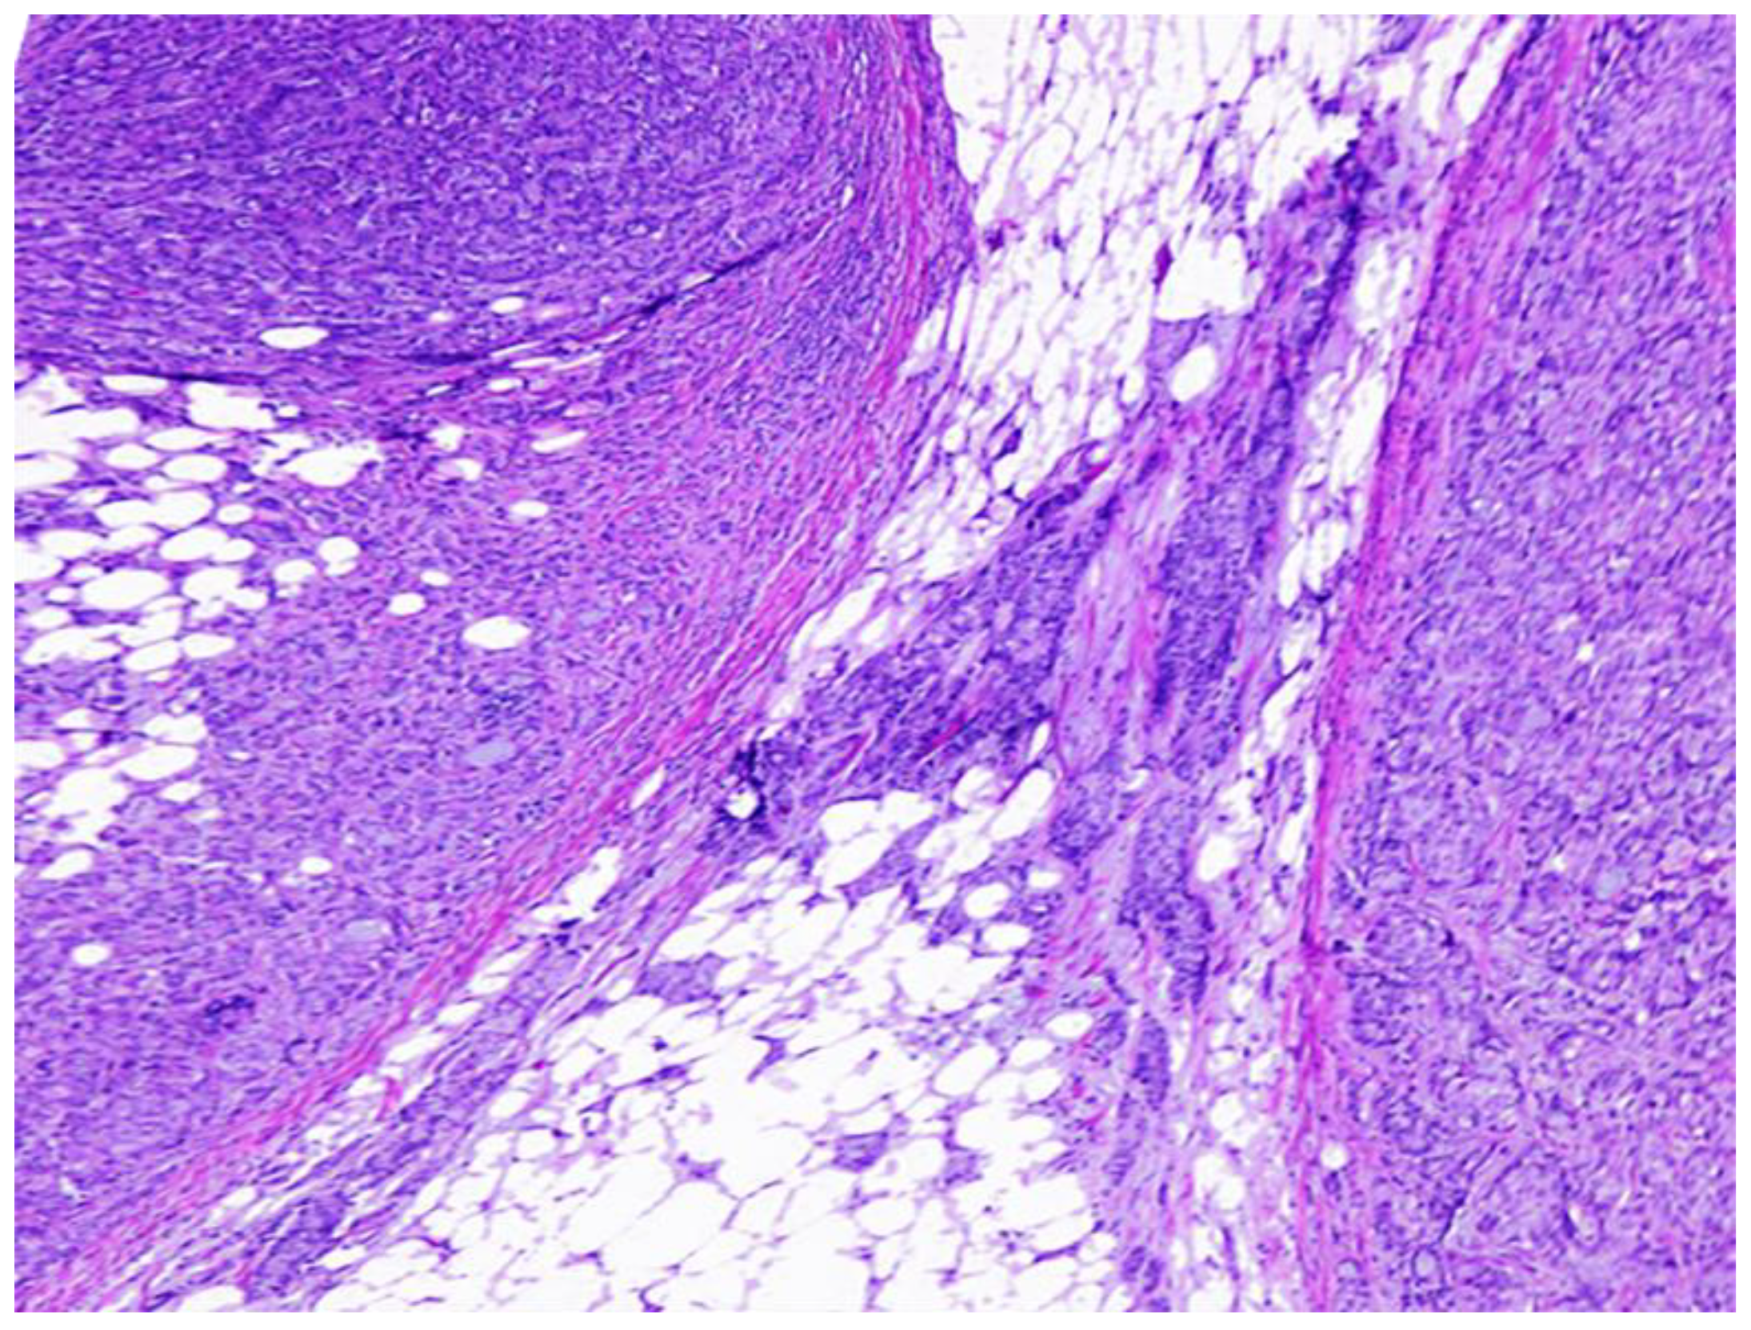

Population. This is a retrolective observational study identifying all consecutive cases of CRC treated with surgery at our institution spanning from 2005 to 2018, culminating in a cohort of 502 patients. A stringent selection process was applied, selecting only the cases presenting with lymph node metastasis; cases with evidence of distant metastasis at initial presentation were excluded, resulting in a refined subset of 255 cases, which correspond to our study group. These cases were further categorized based on their lymph node metastasis status into two groups: (1) those with lymph node metastasis alone (n = 208), and (2) those with lymph node metastasis accompanied by matted nodes (n = 47). Matted nodes were meticulously defined in alignment with the National Cancer Institute’s criteria, characterized as a cluster of fused lymph nodes validated through histopathological examination (https://www.cancer.gov/publications/dictionaries/cancer-terms/def/matted-lymph-nodes, accessed on 1 May 2024). This confirmation was established by the presence of two or more contiguous nodes sharing and adhered by neoplastic cells in their parenchyma and capsules (see Figure 1).

Figure 1. Hematoxylin and eosin-stained slide showing the presence of two contiguous nodes blended by neoplastic cells, which is the definition of matted nodes. Magnification: 40×.